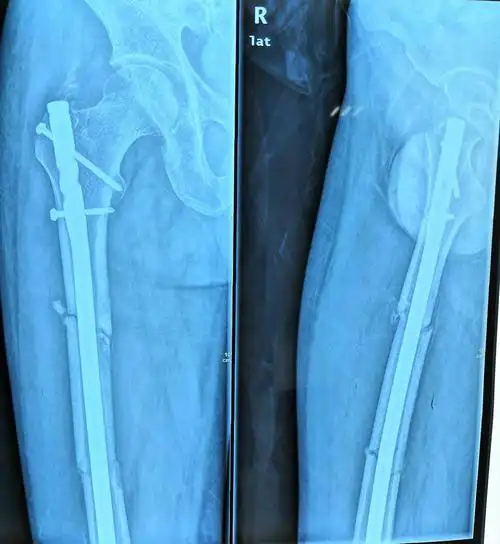

经过2个月的治疗后复查片可见骨折端对位对线良好,已有骨痂生成.

术后三个月,x光片可见骨痂形成,患者恢复良好!家属满意!继续观察!

经过1个月的治疗后复查片可见骨折端对位对线良好,可见大量骨痂生长.

2个月骨痂明显生长